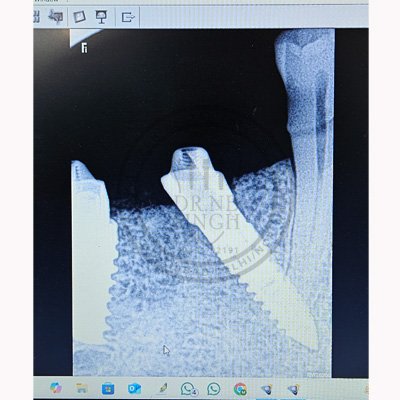

Case – 11 Baleram